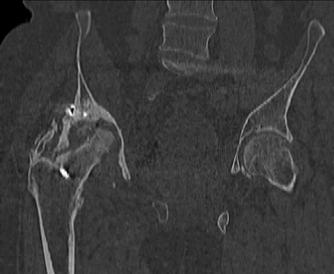

Пациент 49 лет, паровозная травма 23.2.2006, получил вертикальная нестабильное повреждение таза, разрыв левого крестцово-подвздошного сочленения, перелом лонной, седалищной костей слева, T-образный оскольчатый перелом правой вертлужной впадины с переломом заднего края, вывих правого бедра, посттравматическая пояснично-крестцовая плексопатия с обеих сторон, паралич мышц правой голени. В день травмы - вправление вывиха, скелетное вытяжение, 14.3.2006 чрескостный остеосинтез таза. 20.4.2006 остеосинтез правой вертлужной впадины пластинами, осложнившийся нагноением межмышечной гематомы правой ягодичной области. Получал консервативное лечение, было достигнуто полное заживление раны. 24.7.2006 введены илиосакральные винты слева. С декабря 2006 года и по настоящее время ходит на костылях без опоры на правую ногу. Планируется THA. Помогите определиться с вариантом костной пластики? И какую укрепляющую конструкцию использовать?

Мне кажется, будет вполне достаточно кольца Muller, костная пластика из остатков головки чипсами (нужно иметь виду, что собственной головки может не хватить и она может оказаться ненадлежащего качества, поэтому лучше иметь запас аллокости) возможна и структурная пластика, точно алло.

Бесцементная чаша, с восстановлением нормального центра вращения и с костной аутопластикой дна впадины. А Рыков Хабаровск.

Паровозы-элктровозы. Суть не в этом. Сейчас - аутокостная реконструкция вертлужной впадины. Ало - оногда секвестрация. Не надо риска. И, есле готовы технически, эндопротезирование. Лучше бесцесентная чашка прес-фит (допустем - зимет) с дополнительной фиксацией винтами. Возможен вариант кольца Мюллеа. Операцию возможно выполнить в один либо два этапа. Первы -реконструкция вертлужной впадины,а второй - протез через 3-4 мес. Кость лучше брать из гребня, т.к. головка с некрозом-склерозом-фиброзом.